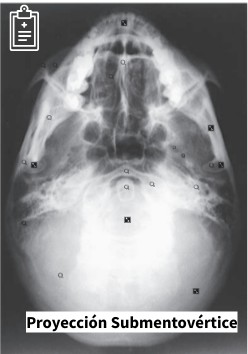

Proyección submentovértice